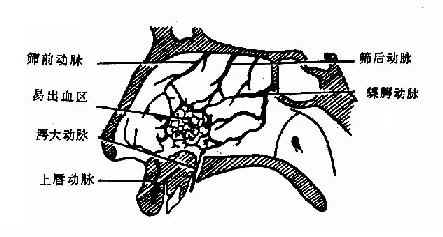

(一)动脉:主要来自颈内动脉的眼动脉(ophthalmic artery)及颈外动脉的上颌动脉(internal maxillary artery),其行径分布如下:

(2)眶下动脉:经眶下孔→鼻腔外壁前段、上颌窦。

(3)腭大动脉:出腭大孔经硬腭向前入切牙管→鼻中隔前下部。

筛前动脉、筛后动脉中隔支、上唇动脉、腭大动脉、鼻腭动脉在鼻中隔前下部构成丰富的动脉丛为鼻出血的好发部位(图1-11)

图1-11 鼻中隔动脉分布